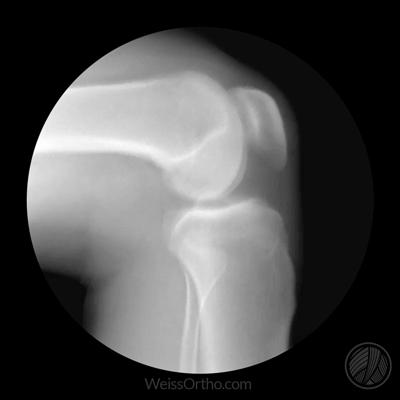

髌骨是我们人体最大的一块籽骨,对于我们的膝关节有非常重要的作用,如果将髌骨切除,我们膝关节伸直的力量将会下降30%左右,这个作用有点类似于杠杆的支点。

在膝关节做屈膝运动的时候,角度达到20度左右,髌骨开始与后方的股骨接触,两者之间开始有压力存在,随着屈膝角度的加大,髌骨与股骨之间的压力也会越来越大。如果膝关节完全伸直,髌骨并不会受到过度的压力,明白以上这两点非常的重要。

一般情况下,髌骨骨折做完手术以后,我们会建议患者适当的进行膝关节的屈伸运动,但是我们会限制角度,一般是控制在0度到30度左右之间,这样的话,髌骨并不会承受大的压力,不会影响骨折的部分,而且也不会造成关节的粘连。但如果患者关节的伤情比较重,关节不能进行正常的屈伸或者是康复介入的比较晚,那么就有可能导致出现膝关节的粘连,患者可能会出现明显的屈、伸膝关节范围受限,而且在进行屈伸关节的时候会有明显的疼痛感。另外有的患者害怕在进行康复锻炼的时候,加大髌骨的压力,导致骨折再次断裂,所以不敢活动,也是导致很多患者出现膝关节粘连的原因。